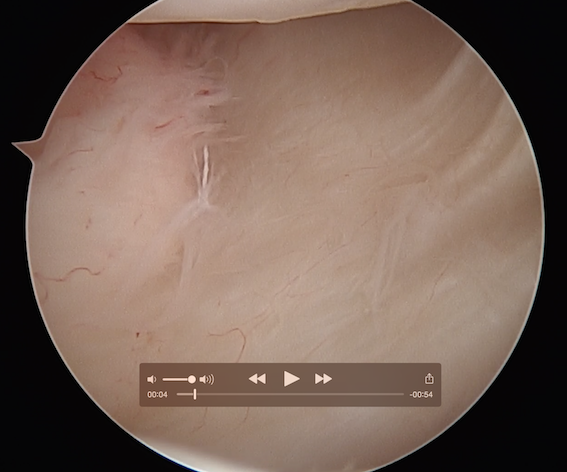

Arthroscopic capsular plication

Technique

Vumedi athroscopic anterior capsular plication

Anterior capsular plication +/- rotator interval closure

- option 1: Suture plicate capsule to labrum

- option 2: Anchors in glenoid and use to plicate capsule to labrum